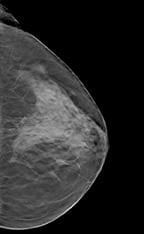

In breast tomo, the X-ray tube and paired detector are driven by a motor to a series of points along an arc. Ultra low-dose exposures at each point create images that are then processed and compiled into a tomogram. Further processing creates a synthetic digital mammogram. Together these two digital images boost diagnostic confidence and reduce patient recalls, while keeping radiation exposure of the patient at the same level as mammography alone.